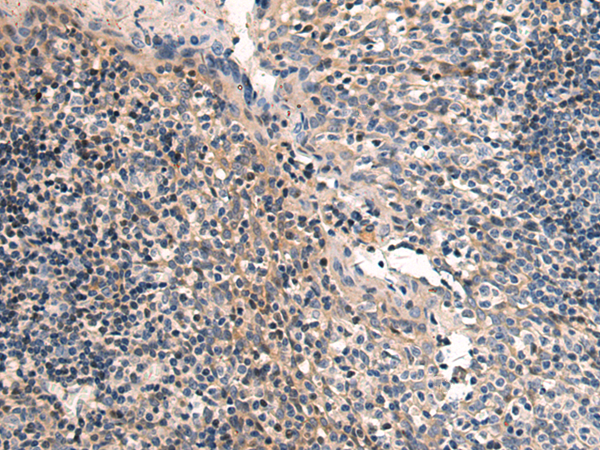

ELISA, IHC |

IHC positive control: |

Human tonsil |

IHC Recommend dilution: |

50-100 |